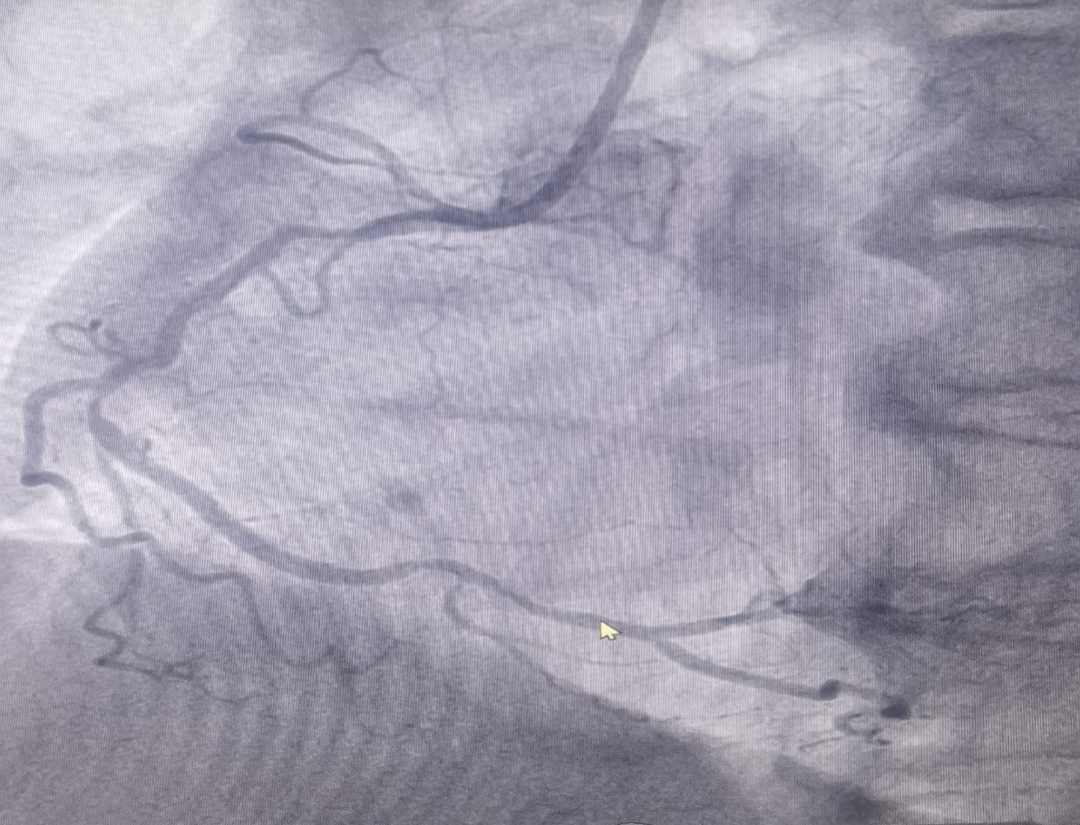

男性患者,72歲,入院診斷為:冠心病,不穩定型心絞痛。冠脈造影結果提示右冠脈重度狹窄,考慮為此次發病的病變血管。

(圖為右冠病變術前影像)